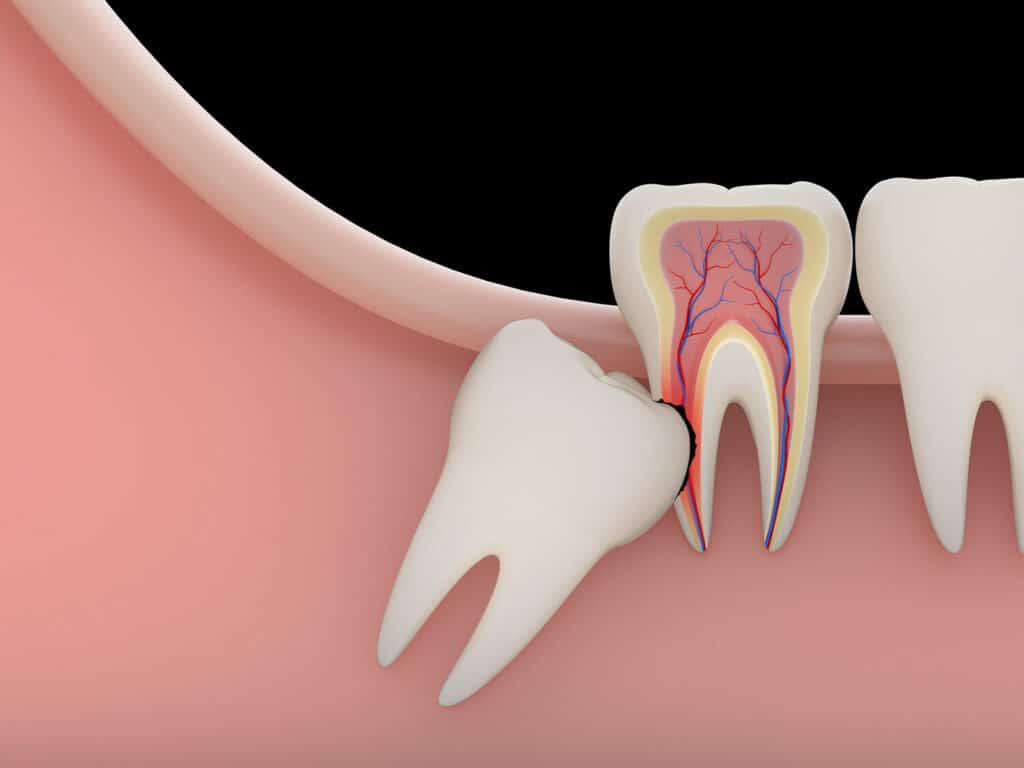

- قد يصبح ضرس العقل بؤرة تسبب الألم بين الحين والآخر نتيجة لضغط ضرس العقل على عصب الفك السفلى ، وقد يمتد الألم إلى الأذن

والعين أو أسنان الفك .

- عندما يكون ضرس العقل مائلاَ على الضرس المجاور يضغط عليه مسببا آلاما شديدة، وفى هذا الوضع المائل تتجمع فضلات الطعام محدثة تسوسا فى كل من الضرسين